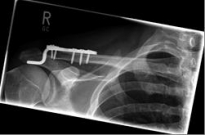

Picture 1 Picture 2

Picture 1: Displaced fracture of the left collarbone before surgery.

Picture 2: After the operation, the fracture is correctly repositioned and held in position with a titanium plate and two screws..